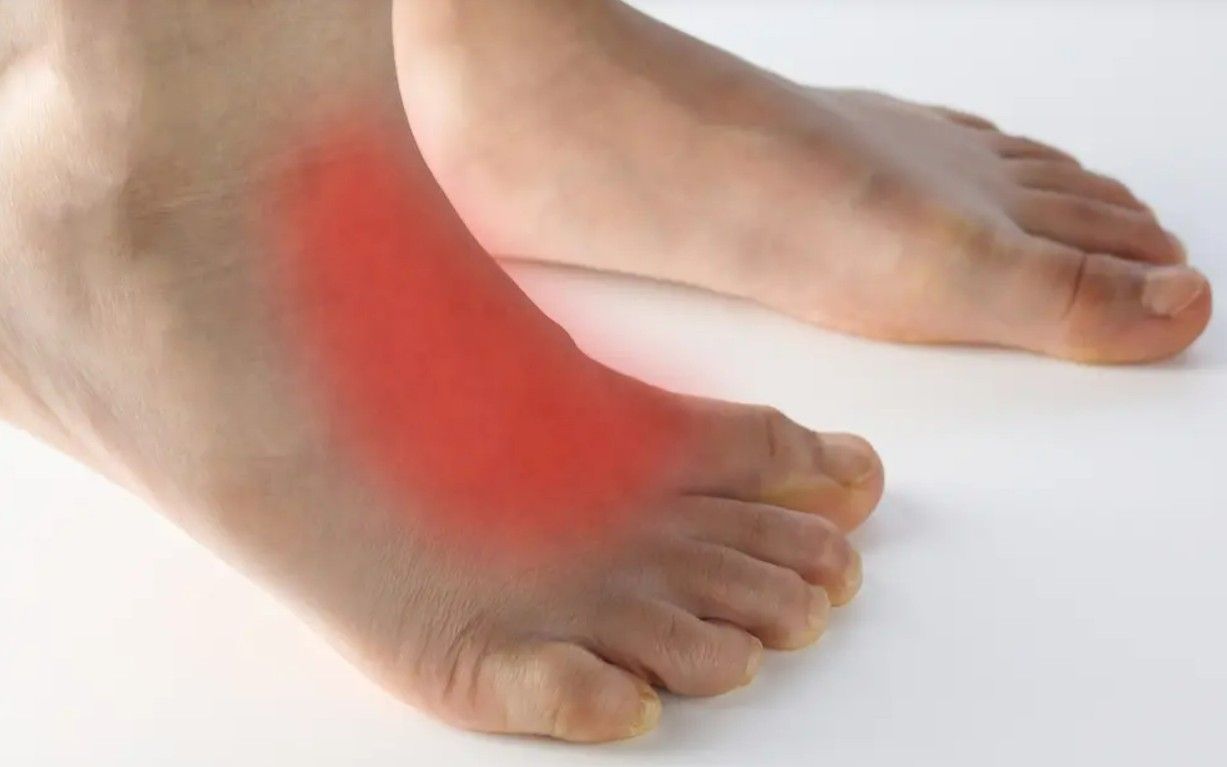

- Dor na região do médio pé: É o sintoma mais comum. Geralmente, piora com a atividade física, após longos períodos em pé ou ao iniciar o movimento depois de um tempo de repouso (a chamada "dor de partida").

- Inchaço: A parte superior ou média do pé pode apresentar inchaço e sensibilidade.

- Sensibilidade ao toque: A área das articulações afetadas pode ficar dolorida ao ser tocada.

- Deformidade: Em estágios mais avançados, podem surgir proeminências ósseas visíveis (osteófitos) ou o pé pode parecer mais "achatado" ou "alargado".